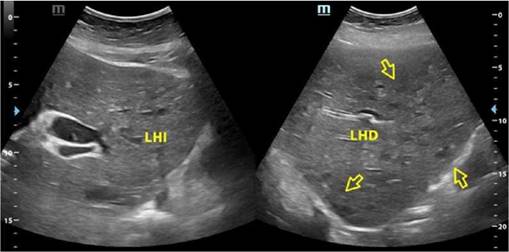

Dentro la evolución del cuadro clínico la paciente presentó una evolución estacionaria, persistiendo con taquicardia, y taquipnea, además de leucocitosis de 19 200 con neutrofolia de 95%, a pesar de haber removido la causa de la obstrucción (coledocolitiasis) y haberse administrado antibióticos (ceftriaxona 1 g EV cada 12 horas y metronidazol 500 mg EV cada 8 horas) durante 72 horas. Es así, que se realiza nueva ecografía abdominal (Figura 2) la cual reportó: “microabscesos hepaticos?, dilatación de vía biliar extrahepática hasta 18 mm y vesícula con barro biliar”, por lo que tras ser valorada por el servicio de medicina interna se decide realizar tomografía axial computarizada (TAC) de abdomen con contraste y en el contexto de una sepsis de foco abdominal por probables microabscesos hepáticos se decide rotar el esquema de tratamiento antibiótico a meropenem 1 g EV cada 8 horas, descontinuando ceftriaxona, y continuando metronidazol 500 mg EV cada 8 horas. En misma fecha se realiza TAC de abdomen con contraste (Figura 3 y 4) la cual reporta: “hepatomegalia, innumerables microabscesos hepáticos, dilatación de vía biliar intra y extrahepatica, a descartar engrosamiento de la pared lateral izquierda de la vesícula biliar, ganglios periportales de etiología por determinar (origen inflamatorio vs metastásico) y mínimo derrame pleural bilateral”. Posteriormente, se solicitan marcadores tumorales de CA 19.9, CA 125, AFP y CEA, todos ellos con resultados dentro de parámetros normales.

Fuente: examen de la paciente realizado en el Departamento de Imagenología del IGBJ. Cochabamba, Bolivia.

Figura 2. Ecografía abdominal que evidencia imágenes hipoecogenicas de diferentes tamaños en lóbulo hepático derecho compatibles con microabscesos (derecha) y persistencia de colédoco dilatado (izquierda).